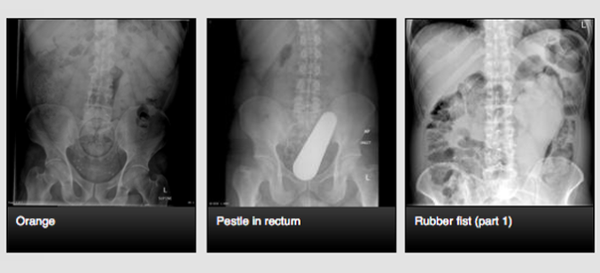

Site reúne raios-x para consulta geral de profissionais

Para pesquisas na internet, geralmente, as pessoas buscam artigos na Wikipedia. Radiologistas procuram em um site um quanto peculiar chamado Radiopaedia. A página reúne imagens de raio-x e, inclusive, mostra partes extremas (e nunca imagináveis) do corpo humano.

A página é um recurso educativo para compartilhar tutoriais e conhecimento sobre tudo que envolve o assunto de radiologia. Para aqueles que não são muito interessados (ou se surpreendem facilmente) por assuntos relacionados a medicina, no topo existe um aviso: “Esse site é dirigido para profissionais médicos e de radiologia, contém conteúdo colaborativo e materiais que podem confundir o público leigo”.

Confira algumas das imagens: